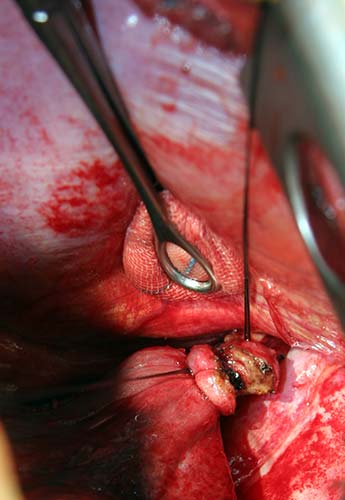

Flexible bronchoscopy revealed normal bronchial anatomy (Video 1). There was no evidence of stricture. All segmental airways were present. A right thoracotomy was performed. The sequestration appeared as a bluish mass incorporated in the substance of the right lower lobe (Figure 6). The artery supplying the sequestration was visualized coursing through the inferior pulmonary ligament and divided (Figures 7, 8; Video 2). Alternating single and double lung ventilation, the sequestration was identified along the basolateral margin of the right lung (Video 3) with a clear line of demarcation. A combination of electrocautery and 4.8mm endoscopic staplers (Video 4) was used to separate normal lung from the sequestration (Video 5). Fibrin glue was applied to all staple lines. Normal bronchial airways were not divided and the remaining lower lobe inflated normally (Video 6). The post-surgical course was uncomplicated and the patient was discharged on post-operative day four. Pathology revealed parenchymal cyst formation with chronic inflammation and organizing pneumonia.

![]() |

| Figure 6: Intraoperative image of bluish-hued sequestration | Figure 7: Feeding artery ligated and partially divided | Figure 8: Cut end of feeder artery off aorta |